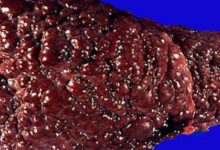

يُحطّم الكبد أغلب الكحول الذي يتناوله الإنسان، ولكن ينجم عن تحطيم جزيئات الكحول مركبات ضارة تُلحق الأذى بخلايا الكبد، وتُضعف المناعة عامة، وتُسبب الالتهابات، وحقيقة يتناسب الضرر الذي يلحق بالكبد تناسبًا طرديًا مع كمية الكحول المتناولة، والجدير بالبيان أنّ أولى مراحل أمراض الكبد الكحولية ما يُعرف بمرض الكبد الدهني الكحولي (بالإنجليزية: Alcoholic fatty liver disease)، وأمّا المراحل اللاحقة فتتمثل بالتهاب الكبد الكحوليّ وتشمّعه (بالإنجليزية: Cirrhosis)، وأمّا بالنسبة لعلاج أمراض الكبد الكحولية فتعتمد على مرحلتها؛ فمثلًا يعتمد علاج المرحلة الأولى (مرض الكبد الدهني الكحوليّ) على الامتناع التامّ عن شرب الكحول، ويمكن طلب المساعدة الطبية في ذلك، وقد يلجأ المختص لوصف أدوية تُقلل اشتهاء الكحول أو حتى تُسبب المرض للجسم في حال شربها، وأمّا بالنسبة لتشمع الكبد فيمكن السيطرة على المشاكل التي يُسببها بوصف أدوية معينة، ولكن إذا وصل الأمر إلى مرحلة الفشل الكبديّ؛ فإنّ زراعة الكبد (بالإنجليزية: Liver Transplant) هي الحل الوحيد لعلاج المشكلة.[٤]